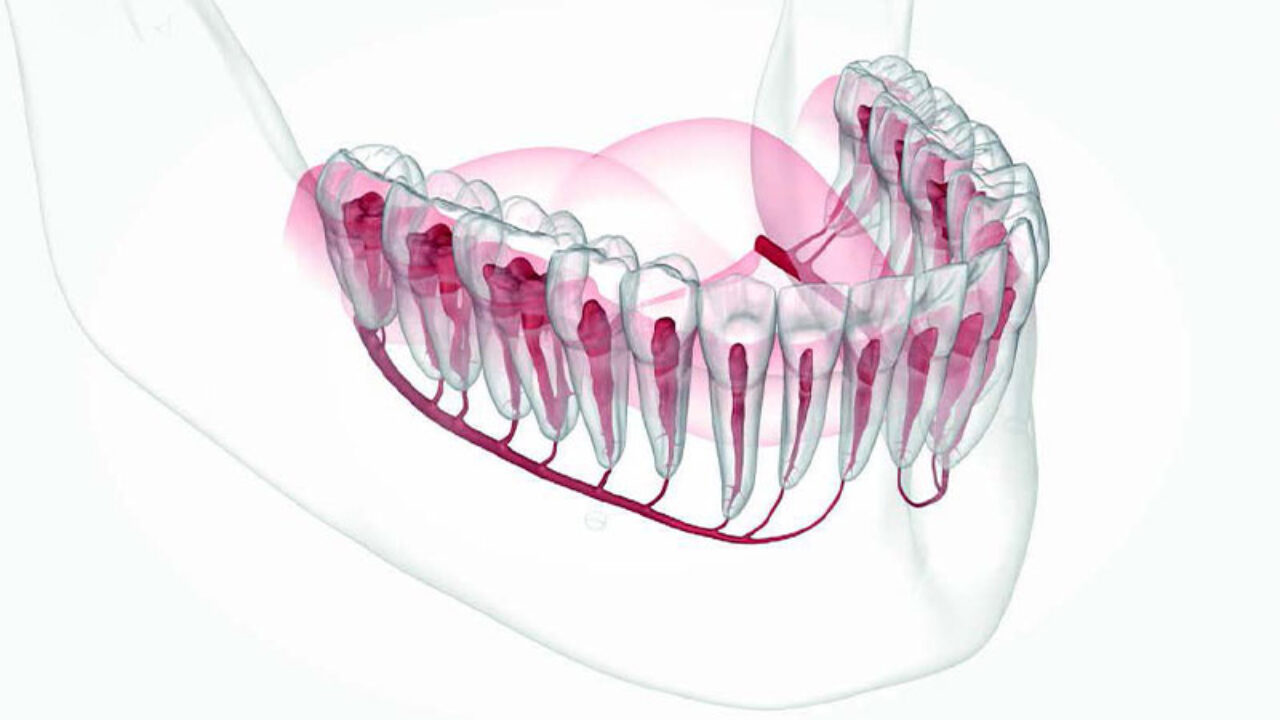

Εικ.1 Ερευνητές στη Φινλανδία δημιούργησαν ένα μοντέλο βασισμένο στην τεχνητή νοημοσύνη που εντοπίζει τα κανάλια της κάτω γνάθου γρήγορα και με ακρίβεια.